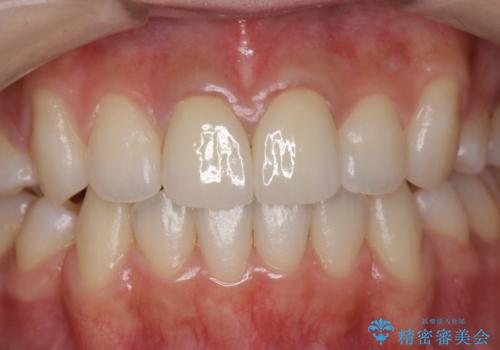

[ジルコニアクラウン治療] 笑った時に目立つ銀歯を白くしたい

![[ジルコニアクラウン治療] 笑った時に目立つ銀歯を白くしたいの症例 治療後](https://seimitsushinbi.jp/wp/wp-content/uploads/2020/07/b5a325afedd469212bae5e25910ae923-500x350.jpg?v=1595071338)